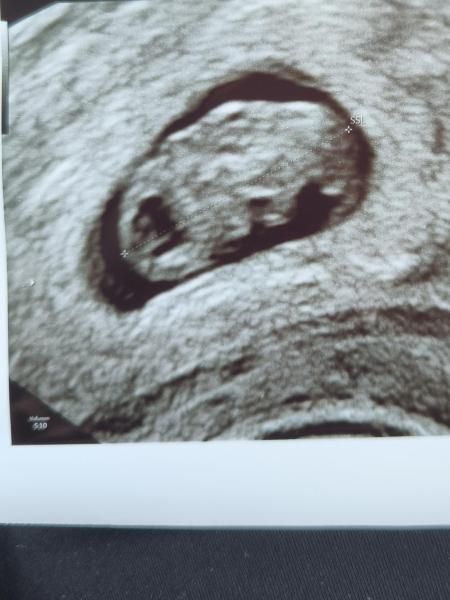

Hallo zusammen Ich hatte heute meinen ersten Termin beim Frauenarzt. Es sieht alles gut aus. Eventuell werde ich noch vor datiert. Das Kleine ist 1,5cm groß. Habe leider leichte braune Schmierblutungen. Muss jetzt Progesteron nehmen und bin für die nächsten zwei Wochen krank geschrieben. Am 05.02. darf ich wieder hin.

Bild zu 1. Frauenarzttermin 7+5 - Forum für September - Mamis